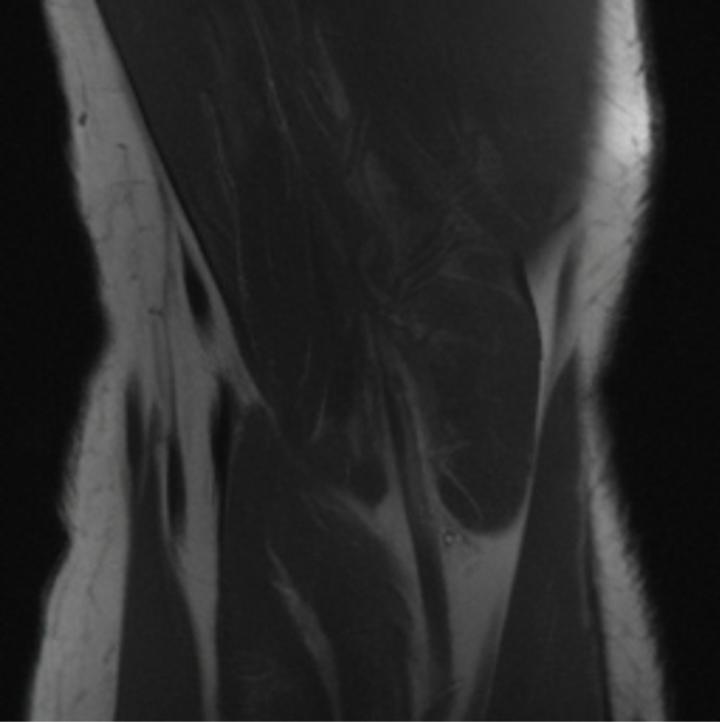

One way to test the generalization capability of the trained X-Diffusion is to test it on a completely different domain from an MRI dataset not seen during training. We report the single-slice results on the test set of knees from NYU fastMRI [33, 80], using the X-Diffusion trained on the BRATS brain MRIs. The test PSNR result is 34.17 and an example is shown in Figure 8. It shows how successfully X-Diffusion can generate knee MRIs (out-of-domain) despite being trained on brains.

Small Knee MRIs clinical study. To qualitatively assess how realistic our generated knee out-of-domain 3D volumes were (produced from a single slice), we gave 20 generated examples alongside their real MRI counterparts to an expert orthopedic surgeon J. F.. He was then asked to identify the real example from a set of 20 MRI pairs. The surgeon correctly identified the real MRI in only 10 out of 20 pairs, could not decide in 3 pairs, and misidentified the generated MRI as real in the remaining 7 pairs. This further validates the generated out-of-domain MRIs.